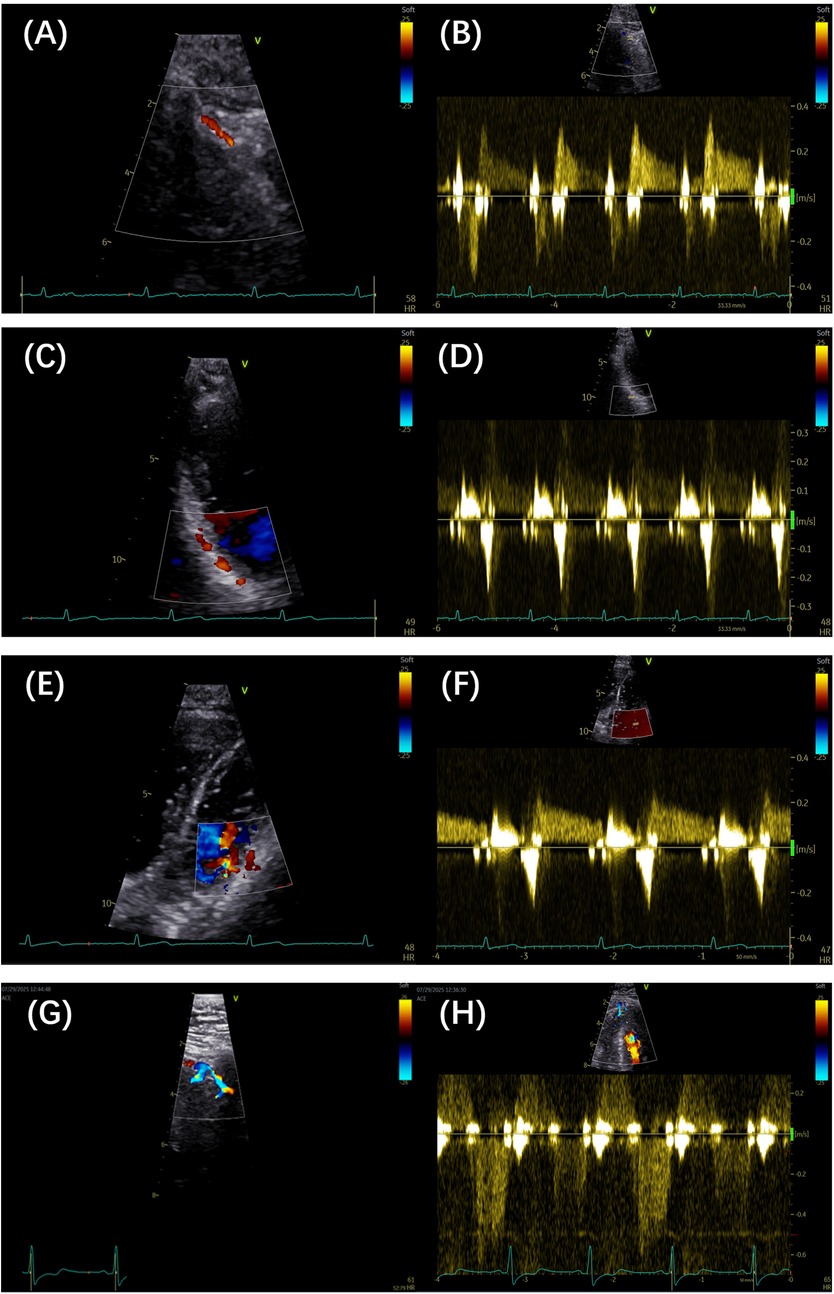

Figure 1

(A,B) Color Doppler and pulse Doppler detection of the LAD artery, respectively. (C,D) Color Doppler and pulse Doppler detection of the PDA, respectively. (E,F) Color Doppler and pulse Doppler detection of the LCX branch, respectively. (G,H) Color Doppler and pulse Doppler detection of septal branches, respectively. LAD, left anterior descending; PDA, posterior descending artery; LCX, left circumflex artery.